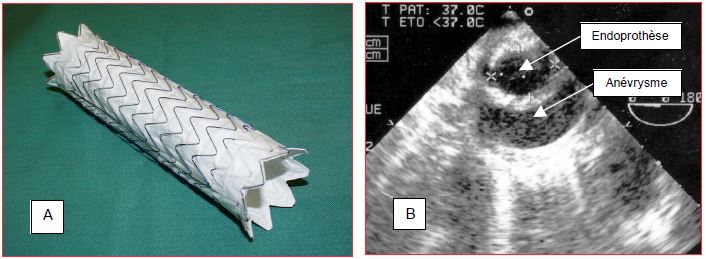

Ponter un anévrysme de manière non invasive avec une prothèse endovasculaire est une idée qui remonte aux années cinquante, mais dont la réalisation pratique date de 1990 [14]. Comparée au remplacement aortique à ciel ouvert, cette technique diminue les pertes sanguines, la morbidité et la durée du séjour hospitalier; elle améliore la stabilité hémodynamique, évite le clampage aortique et autorise l’anesthésie locale ou loco-régionale [1]. La prothèse est un tube de Dacron™ armé imperméable prévu pour durer 10 ans (Figure 18.47).

Figure 18.47 : Endoprothèse aortique. A. Endoprothèse dépliée telle qu'elle se positionne dans l'aorte. B: Image ETO d'une coupe transversale de l'aorte thoracique descendante montrant une endoprothèse en place dans un anévrysme; dans ce cas, elle a pris une forme elliptique (1.75 cm x 2.40 cm).